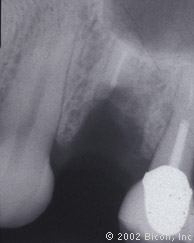

14. | X光片显示即刻负重的种植体。 |